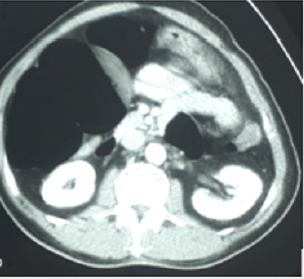

About 7 hours later proceeded with CT abdomen (Computer tomography) of abdomen. It showed a rectal tube in the rectosigmoid colon. There is short segment focal dilatation of the ascending colon with a maximum diameter of 9.4cm. The wall of the affected colonic segment is not thickened. No intramural air or pneumotoses colon. The rest of the small or large bowel loops are not dilated. No ‘whirl signs’ of the mesentery seen. No bowel related mass. No pneumoperitoneum. No ascites. The descending colon appears displaced to the centre of the abdomen. Appendix is normal in appearance. No obvious filling defects seen in the mesenteric arteries.

a) Impression: History of recent distortion of sigmoid colon prior to CT scan. CT Abdomen shows focal dilatation of the ascending colon with no evidence of bowel edema or pneumoperitoneum. No bowel related mass to suggest bowel malignancy.

The patient presented with symptoms of intestinal obstruction. Plain X-ray abdomen revealed a dilatation of localized segment of intestine looked like a shape of an embryo: caecal embro sign (Figure 1) and looks like one of the pictures of caecal volvulus (no.6) of radiology masterclass [8]. However, CT abdomen (ordinary CT) was neither in favour of caecal volvulus nor in favour of appendicitis in this case. Atypical presentation and plain X-ray features of caecal embryo sign mislead to caecal volvulus and management in such line was proceeded. When the abdominal pain was persisting, and laparotomy was carried out and found out to be tip appendicitis attached to the mesentery of small intestine making a hole through which caecum together with small intestine internally herniated resulting small loop obstruction. Juliana M et al. [9] stated that when cecal volvulus is suspected, the absence of distal colonic decompression on CT topograms makes the diagnosis very unlikely. There is short segment focal dilatation of the ascending colon with a maximum diameter of 9.4cm in this patient.